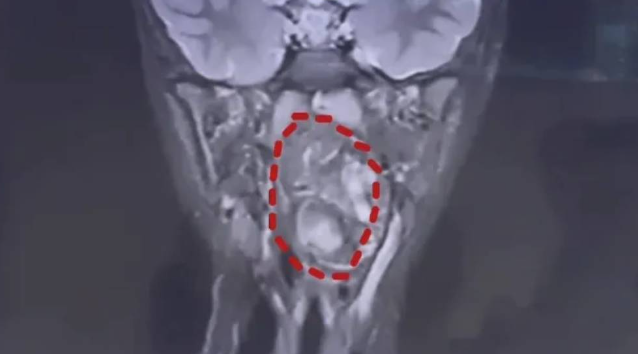

Initial medical checks suggested a possible enlarged adenoid, but further examinations revealed a far more serious condition. Doctors found a tumour roughly the size of a chicken egg situated in the boy’s pharynx. Due to the severity of the case, the family was referred to a specialist children’s hospital in Shanghai for advanced treatment.

Medical assessments showed that the growth had nearly blocked the child’s airway, leaving only a narrow passage for breathing. Experts warned that without urgent intervention, the condition could have led to life-threatening suffocation.

Doctors later diagnosed the mass as a teratoma, a type of germ cell tumour. In a rare finding, specialists explained that the tissue contained elements such as fat and cartilage, suggesting it may have originated from an incompletely developed twin that failed to form normally during early development.